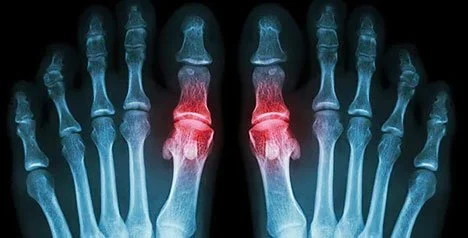

Rheumatoid Arthritis

Rheumatoid arthritis is a form of inflammatory arthritis. Symptoms of Rheumatoid arthritis can range from mild discomfort to severe joint deformity. Rheumatoid arthritis can be a painful and crippling condition if not under regular treatment by a foot doctor in conjunction with a rheumatologist.

With this condition, your joints feel sore, stiff, and swollen. The pain and inflammation may come and go. Podiatrists have noted that the condition affects your body symmetrically. So, for example, both feet suffer the same symptoms simultaneously. Although the condition afflicts both sexes, females have a much higher incidence of the disease.